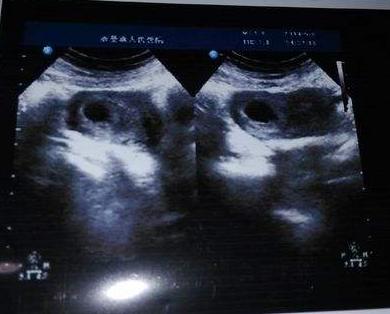

情况一:胎囊的形态

当女性知道自己怀孕后,在两个月左右会第一时间去医院检查宝宝是否发育健康。而在这个时候,我们通过B超单可以看到宝宝的孕囊形状,事实上我们可以通过宝宝的孕囊形状来判断宝宝的性别,如果孕囊形状偏向长方形,那么很可能说明你妈肚子中怀的男宝机率高一些,但是如果发现宝宝的胎囊形状属于正方形或者是椭圆形,那么这时可能孕妈怀女宝的几率比较大一些。听说这一个方法比较准,孕妈们可以拿出自己的B超单,观察一下宝宝的胎囊形状。